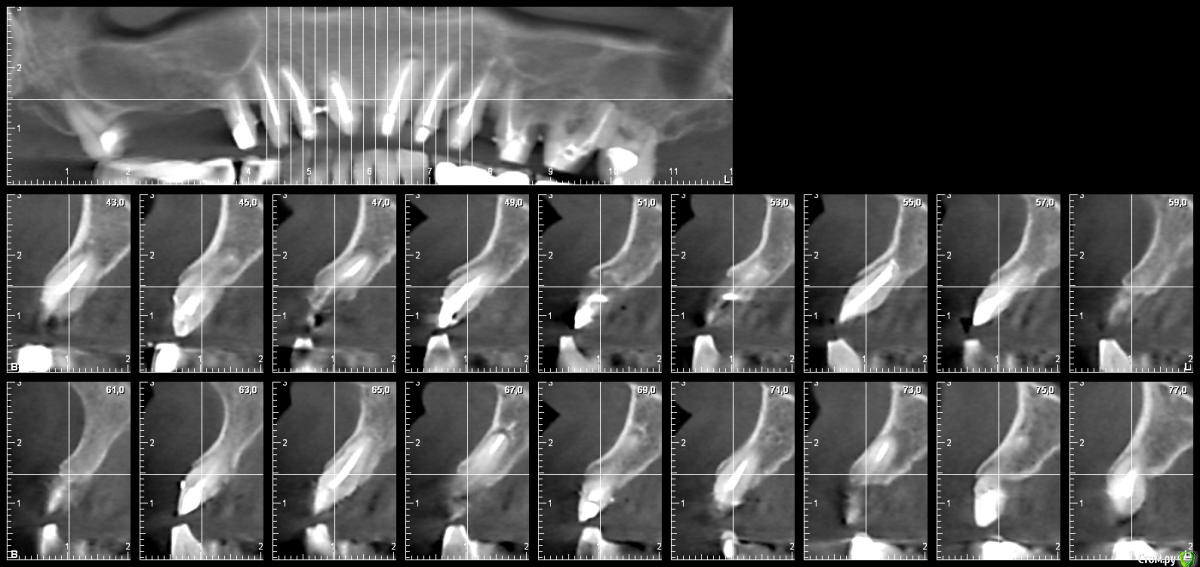

Alexandr1984 Опубликовано 31 марта, 2016 Автор Поделиться Опубликовано 31 марта, 2016 Вот такая картина на кт! Ссылка на комментарий

Alexandr1984 Опубликовано 31 марта, 2016 Автор Поделиться Опубликовано 31 марта, 2016 А почему не срастется?Длина корней и без того маленькая. Если еще поднять на 1-1,5 мм ослабится стабилизация в кости. При этом хочется одиночек.. Ссылка на комментарий

Alexandr1984 Опубликовано 31 марта, 2016 Автор Поделиться Опубликовано 31 марта, 2016 В тупик ваш вопрос ставит, а как оттиски снять, как зафиксировать нормально при таком раскладе, для этого и нужна пародонтальная хирургия, облегчает она работу.Я понимаю о чем вы! Но!!! Как быть если удлинение не состоятельно? Снимать оттиски как раньше снимали) и надеяться на техника) а фиксировать на цемент, убирать излишки наиболее тщательно. Как я ответил коллеге, высота корней мала для таких манипуляций. сегодня оптг прикреплю.. Ссылка на комментарий